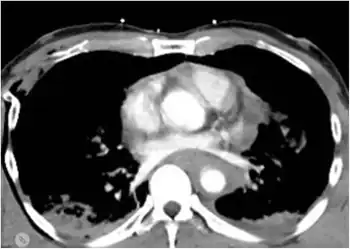

The classical findings on a chest X-ray will be widened mediastinum,[4] apical cap, and displacement of the trachea, left main bronchus, or nasogastric tube. A normal chest x-ray does not exclude transection, but will diagnose conditions such as pneumothorax or hydrothorax. The aorta may also be torn at the point where it is connected to the heart. The aorta may be completely torn away from the heart, but patients with such injuries rarely survive very long after the injury; thus it is much more common for hospital staff to treat patients with partially torn aortas.[1] When the aorta is partially torn, it may form a "pseudoaneurysm". In patients who do live long enough to be seen in a hospital, a majority have only a partially torn blood vessel, with the outermost adventitial layer still intact.[2] In some of these patients, the adventitia and nearby structures within the chest may serve to prevent severe bleeding.[2] After trauma, the aorta can be assessed by a CT angiogram or a direct angiogram, in which contrast is introduced into the aorta via a catheter.